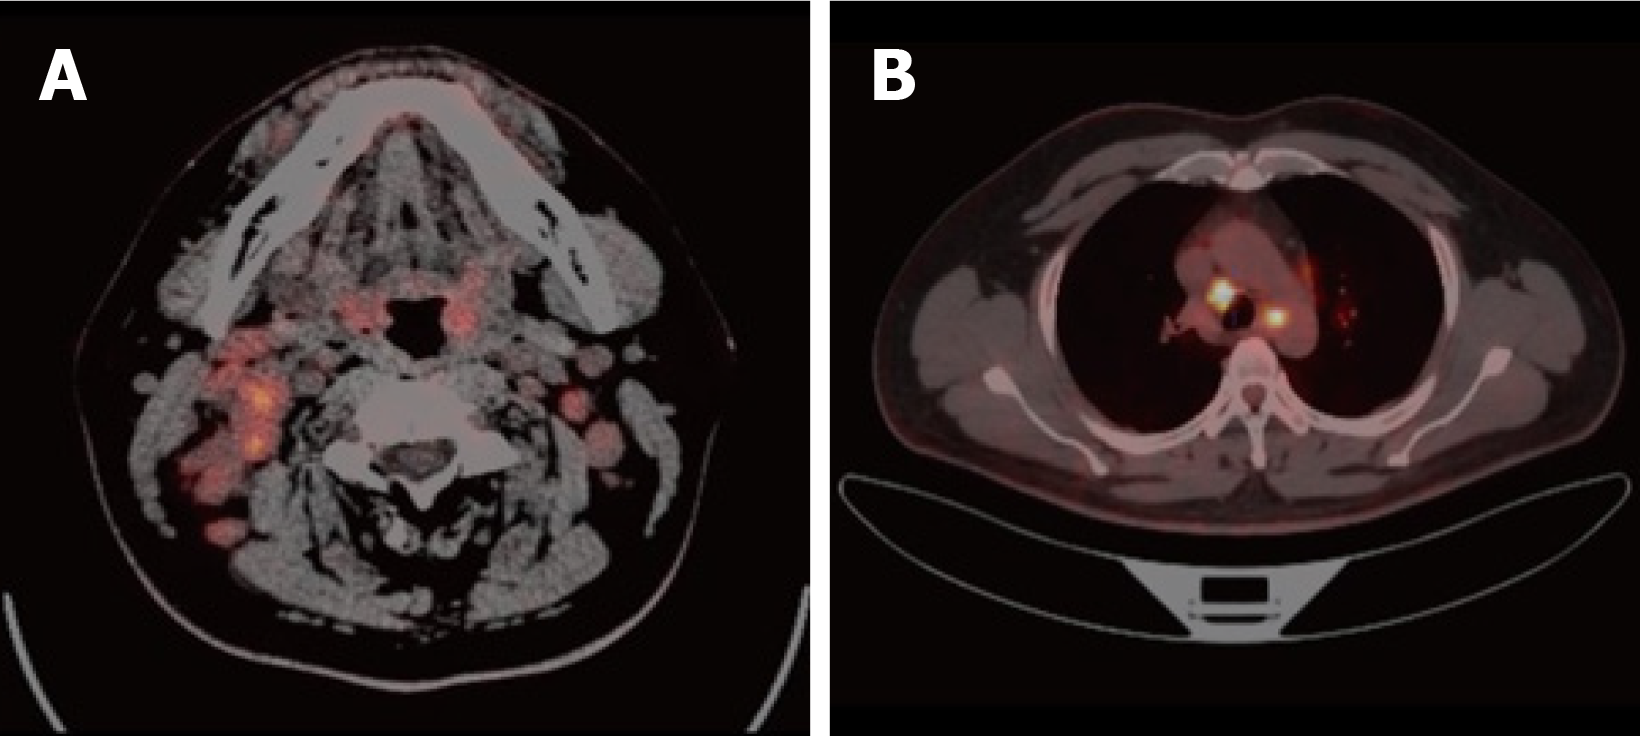

Figure 1 Positron emission tomography/computed tomography findings (July 5, 2022).

A: (Head and neck) Thickening of soft tissue in the posterior wall of the nasopharynx, accompanied by a slight increase in glucose metabolism; Multiple enlarged lymph nodes in the bilateral walls of the oropharynx and bilateral parapharyngeal spaces, accompanied by increased glucose metabolism; B: (Pulmonary hilum and mediastinum) Multiple enlarged lymph nodes in the mediastinum and bilateral hilum, accompanied by increased glucose metabolism.